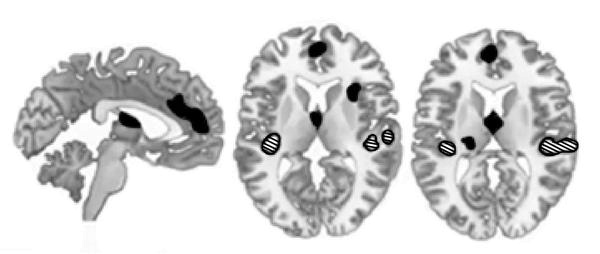

Ниже, на рис. № 3, вы видите сдвоенную томограмму мозга человека, слушающего смех.

В исследовании Скотт испытуемым надевали наушники и транслировали через них различные звуковые сигналы, среди них были и разные виды смеха – как наигранный смех, так и естественный. И вот, что выяснилось:

• когда испытуемые слышали в наушниках естественный и спонтанный смех, реагировала их слуховая кора, причём в очень специфических областях, которые словно бы специально для этого и предназначены;

• когда же испытуемым транслировали в наушники неискренний смех (так мы смеёмся, «потому что надо» – например, для создания благоприятного впечатления о себе), у испытуемых, напротив, активизировались зоны мозга, ответственные за интеллектуальную деятельность – то есть, их мозг чуял неладное и пытался разгадать истинные мотивы того, кто решил обмануть его наигранным смехом.

Иллюстрация к книге — Троица. Будь больше самого себя [i_003.jpg]

Рис. № 3. Результаты томографии мозга при естественном и наигранном смехе (S.K.Scott et al., 2014)

Примечание: зоны, активизирующиеся при восприятии естественного смеха обозначены штрихами, а зоны, активизирующиеся при восприятии наигранного смеха обозначены чёрным цветом.

Иными словами, наш мозг всегда пытается разгадать истинную причину смеха, который мы слышим. И он делает это автоматически, если смех естественный, а если нет, то он анализирует ситуацию, стараясь уловить контекст – что значит этот смех, почему человек смеётся, чего он хочет этим добиться, какая у него цель? Очевидно же, что неспроста!